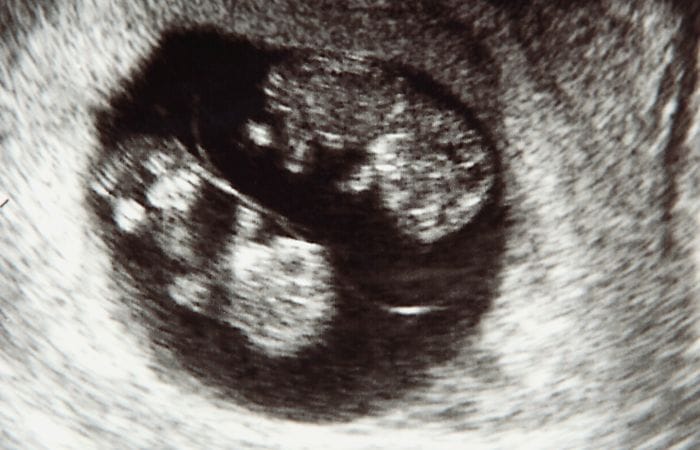

Our specialists use advanced tools to assess maternal and foetal health, including detailed ultrasound scans to evaluate foetal growth and amniotic fluid levels, Non-Invasive Prenatal Testing (NIPT) to screen for chromosomal conditions, and Glucose Tolerance Tests (GTT) to identify gestational diabetes.

Pre-eclampsia screening helps assess the risk of pregnancy-induced hypertension, while foetal Doppler studies monitor blood flow and detect any signs of distress in the baby. These assessments enable us to tailor care plans to each patient’s specific needs, promoting safer outcomes for both mother and child.